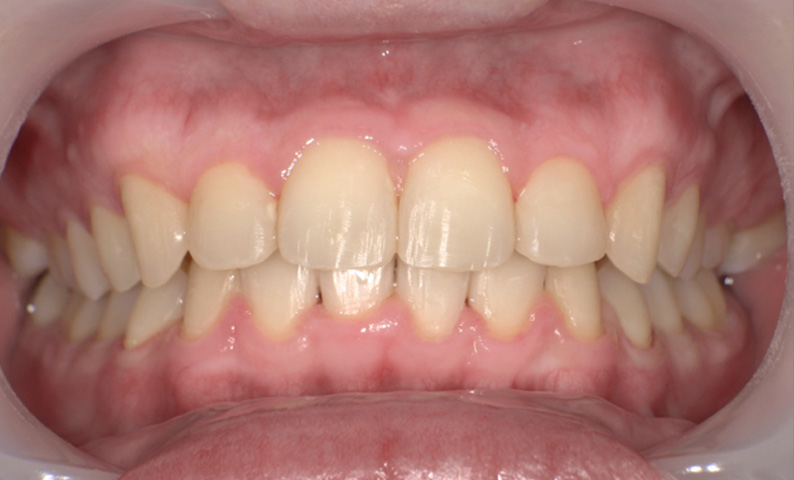

症例_009 「上下の前歯」症例

治療期間:7ヶ月金額:54万円+税20代女性捻転歯一部の反対咬合前歯のガタガタ